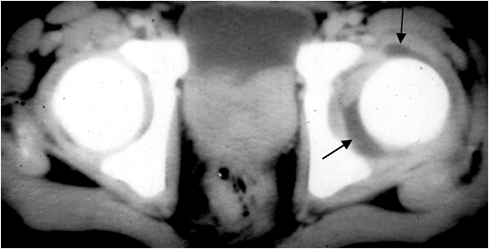

Fig 57 A. Artritis aguda.

TAC axial. Aumento del espacio articular y detección de líquido en la cadera izquierda, por artritis infecciosa.